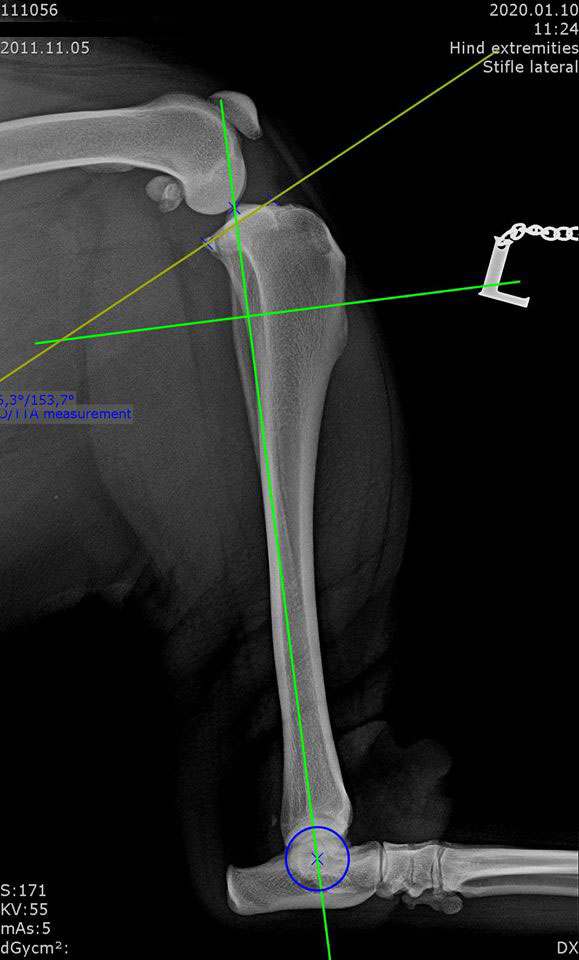

Shar-pei, cruciate ligament rupture surgery, TPLO with small pre-contoured polyaxial plate.

Sawed with R21 blade. Temporary fixation with 1,4 mm K-wire through the plate’s micro hole, which helps untill the locking poliax screws are driven in.